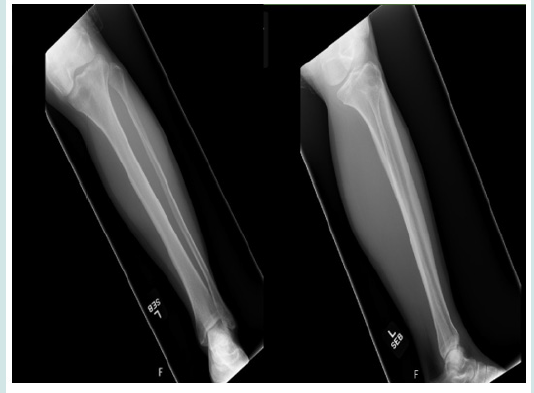

CM was a 67-year-old female runner presenting for an initial evaluation of left ankle and distal medial shin pain. Her pain was primarily present when running and she experienced a deep sharp pain in her shin, with a 5/10 score on the numerical pain scale (NPS). On physical exam, her tibia was tender to palpation with a small prominence over the distal medial aspect. She arrived to clinic with prior recent X-ray, ordered by her primary care physician. As seen in (Figure 1), her X-ray results were unremarkable for any pathology. Next, diagnostic MSK US was performed using the General Electric Logiq E R6 Portable Ultrasound machine, with a high-frequency linear transducer positioned over her area of tenderness on the distal tibial metadiaphysis. Her MSK US exam revealed a frank cortical break in the distal tibia, as seen in (Figure 2). Additionally, she experienced tenderness to sonopalpation. Due to a high clinical suspicion for a stress fracture, an MRI was ordered. She was recommended to strictly avoid weight-bearing activity for [5,7] days and was advised to avoid running for [4,6] weeks, with a gradual return to running through a walk-run program at physical therapy.

Figure 1: Normal radiographs (X-rays) of left lower leg in the anterior-posterior (AP) and lateral orientations with no osseus defects detected.